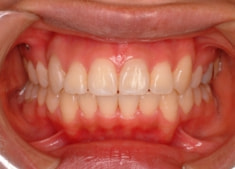

治療後(2年3ヶ月後)